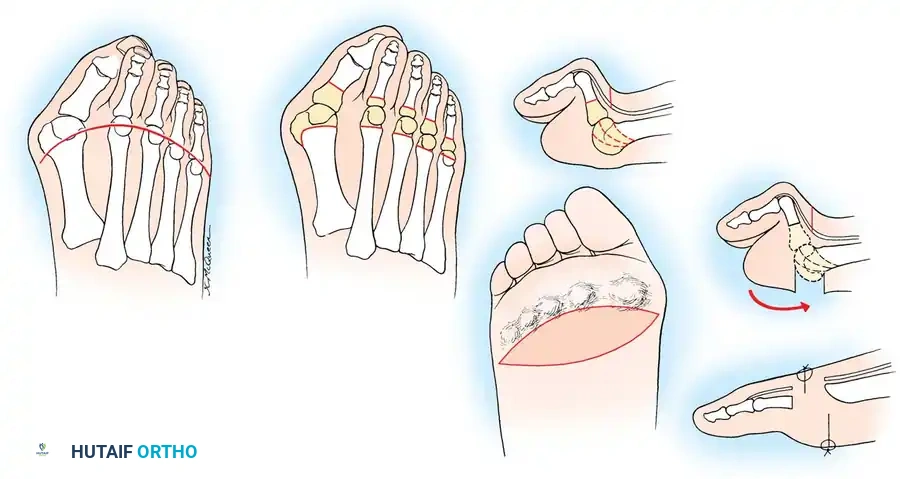

Step 3: Lesser Metatarsal Head Resection

- Approach: Two dorsal longitudinal incisions are typically utilized (one centered between the 2nd and 3rd rays, and one between the 4th and 5th rays) to access all lesser MTP joints while preserving dorsal skin bridges. Alternatively, a transverse plantar approach can be used if severe plantar callosities require excision.

- Resection: The extensor tendons are retracted or lengthened (Z-plasty). The dorsal capsule is opened, and the collateral ligaments are sharply divided to allow plantarflexion of the metatarsal.

- Osteotomy: An oscillating saw is used to resect the metatarsal heads at the anatomical neck. It is imperative to create a smooth, parabolic cascade (the 2nd metatarsal should be the longest, tapering down to the 5th).

- Soft Tissue Balancing: The plantar plate and fat pad, which have migrated distally, are mobilized and pulled proximally under the remaining metatarsal stumps. If the toes remain contracted, closed osteoclasis or PIP joint resection arthroplasties may be performed.

- Pinning: Smooth Kirschner wires (K-wires) are driven antegrade through the toes and retrograde into the metatarsal shafts to hold the toes in neutral alignment.

The hyperextension and eventual dislocation of the MTP joints yield several clinically significant and highly symptomatic deformities:

- Distal Migration of the Plantar Fat Pad: As the proximal phalanx dislocates dorsally, it drags the plantar aponeurosis and the protective plantar fat pad distally.

- Intractable Plantar Keratoses (IPKs): The metatarsal heads are left completely uncovered and prominent against the plantar skin, leading to painful callosities and a high risk of skin ulceration.

- Soft Tissue Balancing: The plantar plate and fat pad, which have migrated distally, are mobilized and pulled proximally under the remaining metatarsal stumps. If the toes remain contracted, closed osteoclasis or PIP joint resection arthroplasties may be performed.